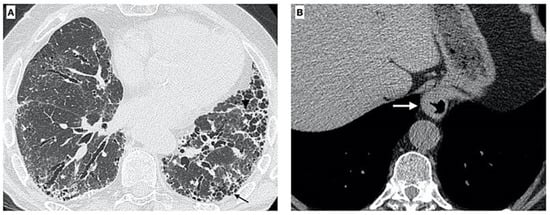

A barium esophagram, esophageal endoscopy, and high-resolution CT can help to describe the anatomy of the esophagus in relationship to the diaphragm and find the location of the LOS [61,62,63,64,65,66]. Different studies reported the presence of HH in between 39% and 53% of IPF patients, according to the method of CT interpretation [42,62]. HH may increase the probability of IPF due to easier microaspiration in affected patients. Lee et al. [62] found measurable concentrations of pepsin in the BALF of IPF patients, suggesting that these episodes may be frequent in these patients (Figure 1).

Figure 1. Axial chest CT images of a 73-year-old male with established IPF. (A) High-resolution image shows fibrotic changes due to the presence of diffuse irregular thickening of interlobular septa, traction bronchiectasis/bronchiolectasis, and honeycombing (black arrow); moreover, distortion of oblique fissure is visible. (B) CT also demonstrates the presence of a gastric (thoracic) hiatus hernia (white arrow).